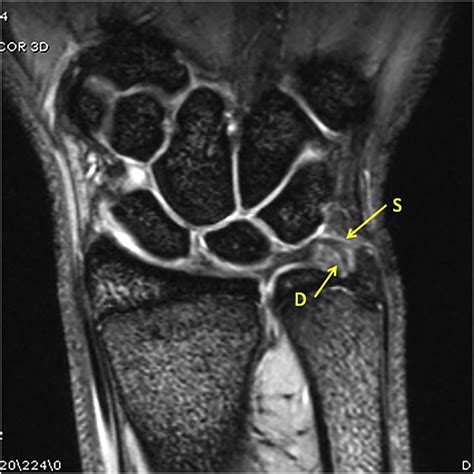

Diagnosing a TFCC tear involves a combination of a physical examination and imaging studies. A doctor will typically perform the TFCC Load Test, where they compress the wrist while rotating it to see if it reproduces pain. Because X-rays do not show soft tissue, they are often used to rule out fractures. For a definitive diagnosis, an MRI (Magnetic Resonance Imaging) is the gold standard, as it provides a clear view of the cartilage and ligaments.

MRI Visualizes the tear within the cartilage complex.